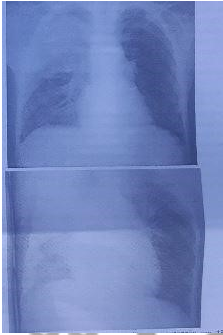

Escolar de 8 anos procura serviço de saúde com quadro de febre aferida e tosse há cinco dias. Exame físico: afebril, frequência respiratória de 50 ipm, desconforto respiratório moderado. Ausculta pulmonar: murmúrio vesicular diminuído em hemitórax direito, com estertores crepitantes em ápice e 1/3 médio também à direita. Radiografia visualizada abaixo. Qual a melhor conduta neste momento (conforme imagem do caderno de questão)?